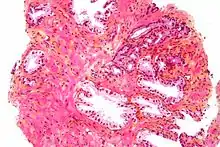

Microanatomy

The prostate consists of glandular and connective tissue.[1] Tall column-shaped cells form the lining (the epithelium) of the glands.[1] These form one layer or may be pseudostratified.[3] The epithelium is highly variable and areas of low cuboidal or flat cells can also be present, with transitional epithelium in the outer regions of the longer ducts.[9] The glands are formed as many follicles, which in drain into canals and subsequently 12–20 main ducts, These in turn drain into the urethra as it passes through the prostate.[3] There are also a small amount of flat cells, which sit next to the basement membranes of glands, and act as stem cells.[1]

The connective tissue of the prostate is made up of fibrous tissue and smooth muscle.[1] The fibrous tissue separates the gland into lobules.[1] It also sits between the glands and is composed of randomly orientated smooth-muscle bundles that are continuous with the bladder.[10]

Over time, thickened secretions called corpora amylacea accumulate in the gland.[1]

Microscopic glands of the prostate